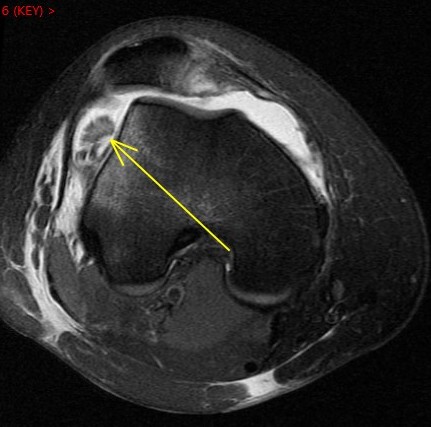

Figure 4 for case Patellar dislocation

Figure 4

Discussion

All the classic findings. Im showing this one because of the loose chondral body knocked off of the patella. Nice example.

Patellar dislocation